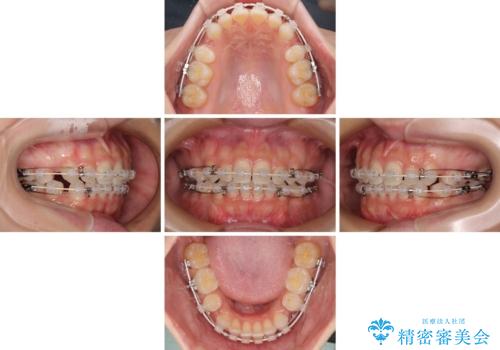

前歯のデコボコとクロスバイト ワイヤー装置での抜歯矯正

- 前歯のデコボコとクロスバイトを気にして来院された患者様です。

上下ともにデコボコはそれほど強くありませんでしたが、非抜歯では口元が突出した仕上がりとなる可能性があるため、上下左右の第一小臼歯4本を抜歯し、ワイヤー装置での抜歯矯正を行うこととしました

スペースを閉じるために期間を要しましたが、無事に綺麗な口元に仕上げることができました。